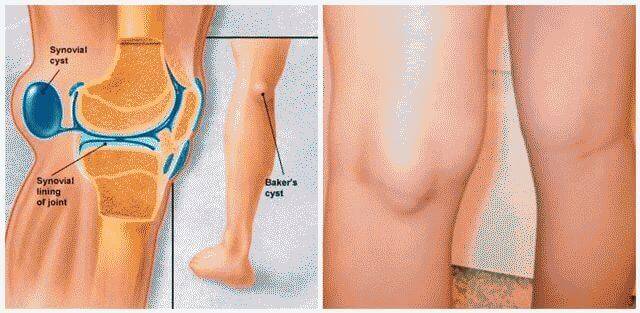

Фото и диагностика кисты Бейкера